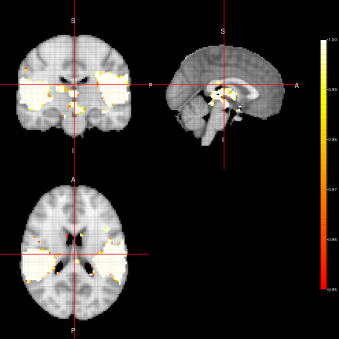

AG-algorithm(ACE-FEST) AG-algorithm(ACE-FFBS)

Refer to caption Refer to caption

AG-algorithm(ACE-FSTS)

Refer to caption

Figure 5: Activation Maps obtained for the ”voice localizer” example when using the AG-algorithm

In figure 5, we can see group activation maps obtained when using the AG-algorithm for every sampler option (FEST, FFBS, FSTS) at the individual level. From this example, we can conclude that with the AG-algorithm it is also possible to identify brain activation when analysing fMRI data for group activation.